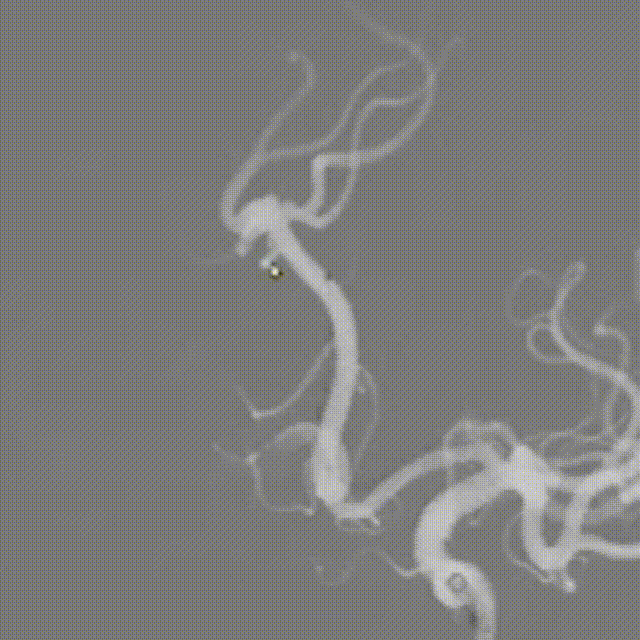

微导管到位。

交换FLOPPY导丝,提高支撑力,带高中间导管。

输送球囊到位、充盈及泄压。

撤出球囊后造影。

支架微导管到位。

支架到位。

支架全段打开。

支架全段打开造影。

回撤推送导丝及微导管。

术后造影。

术后正侧位造影。

术后VASO CT。

强易达(Choydar)血流导向密网支架材质是镍钛合金,输送易到位;头端导丝、50%释放点、100%释放点清晰,便于观察支架位置。

50%Mark点可帮助分析后半段打开后的尾端位置,近端血管较粗考虑支架短缩,也可调整支架的50%Mark点置于偏近端一些。

支架由2对4根铂钨合金显影丝以对向排列的方式,混合编入支架主体,呈3D立体显影效果,便于观察支架贴壁情况。